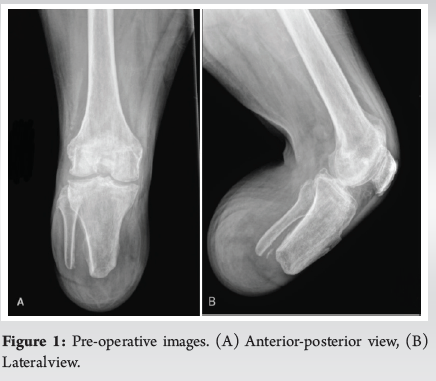

Case Report: Total Knee Arthroplasty in Ipsilateral Below-Knee Amputee

Christopher E Marrero , Jonathan Willard ………………………………p.07-12